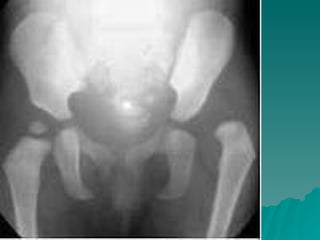

Developmental dysplasia of the hip is a condition where the hip joint is unstable or partially dislocated. It affects 1-50 out of every 1000 live births, with 60% being detected by 1 week of age and 90% by 8 weeks. The document discusses the anatomy, aetiology, pathology, clinical features, imaging, and different treatment approaches depending on if the patient is under 6 months, 6 months to 6 years, or above 6 years of age.